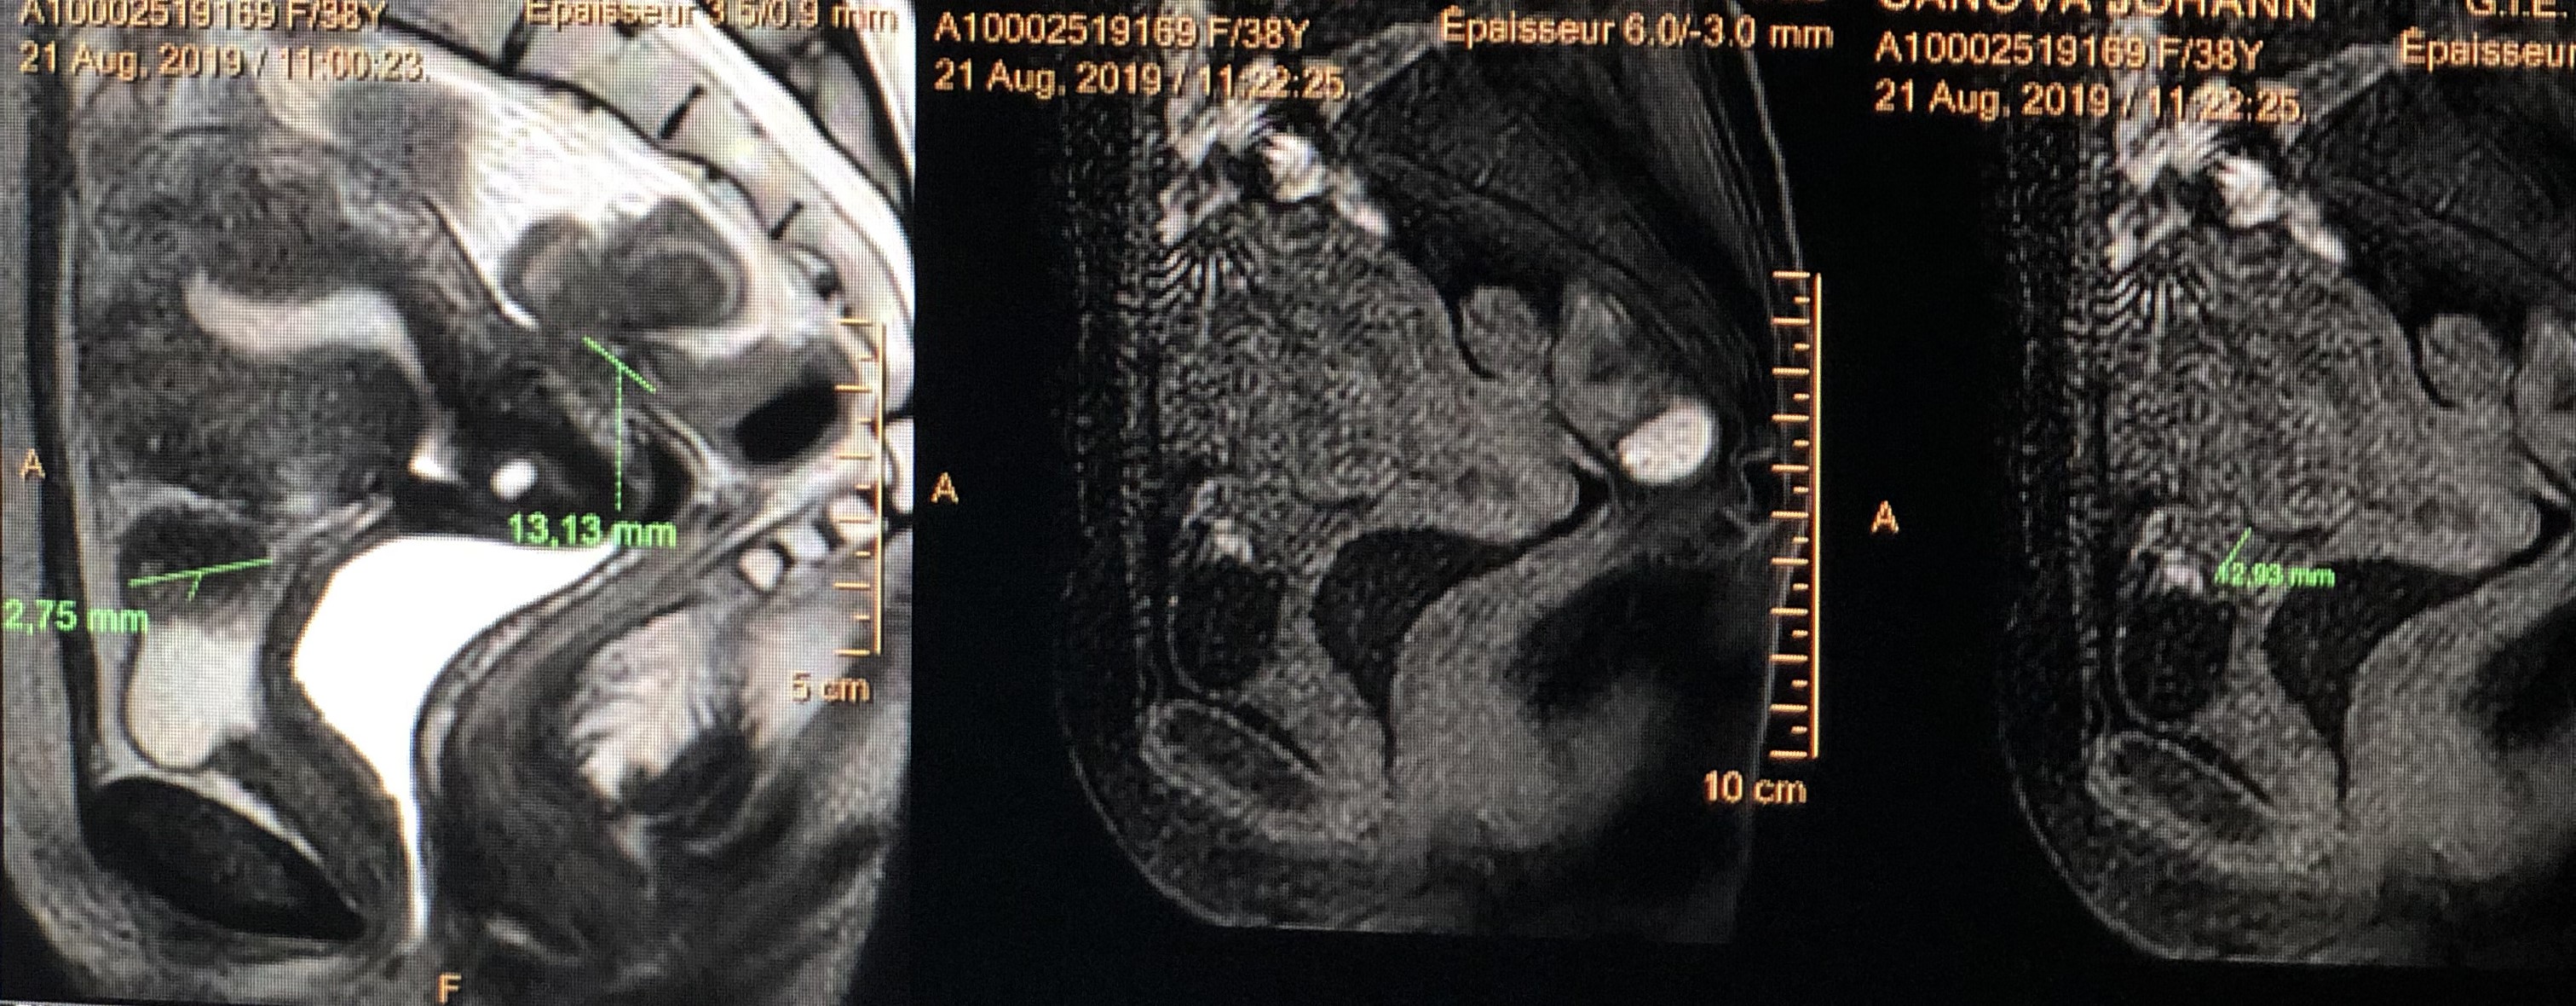

Polype utérin bénin

Schwanome du nerf crural gauche au contact du psoas

Endométriose vésicale et profonde